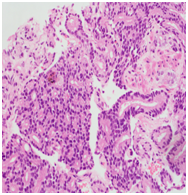

Trans-rectal ultrasound guided biopsy of the prostate confirmed the adenocarcinoma Gleason score 9 (4+5), while the mandibular lesion biopsy revealed metastatic prostate adenocarcinoma (Figures 6–8).

Figure 7 & 8 Prostate biopsy.